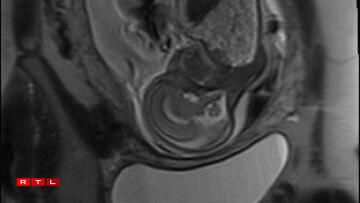

Lis was therefore referred to the Centre Hospitalier de Luxembourg (CHL), where further examinations led to a diagnosis. Noa was found to have a congenital pulmonary airway malformation (CPAM). Doctors explained that a large mass of cysts had formed in his chest, compressing his heart and disrupting his circulation. This, in turn, caused the fluid retention observed during the initial scan.

In Noa’s case, the CPAM was caused by a malformed aorta: a blood vessel had branched toward the lungs and was feeding the cysts. The condition is known as a sequestration. Professor Kohl proposed the following intervention:

“He would go through my abdomen with two small incisions to reach the amniotic sac, then pass through Noa’s chest to the heart, where he would cauterise the blood vessel that was feeding the cysts using a small electric current. From there, we could hope that the cysts would shrink and the lung could begin to develop”.